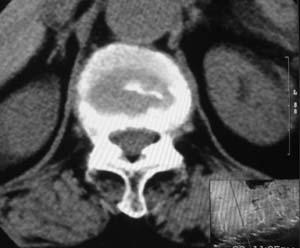

患者,女,72岁,胸背部疼痛3月余,无明显外伤史。曾应用局部封闭、非甾体类止痛药治疗效果不明显,近来疼痛缓解频感背困,平卧缓解,近日行ct检查发现胸12椎体病变,烦请同道发表意见,诊断什么?有何治疗经验!谢谢!!!

标绘图示:第十二胸椎级第一腰椎椎体楔形改变。ct扫描示:第十二胸椎椎体骨质结构紊乱,并可见一囊状低密度影,边缘可见硬化,椎体皮质完整。

考虑:第十二胸椎陈旧性骨折、许莫氏结节。